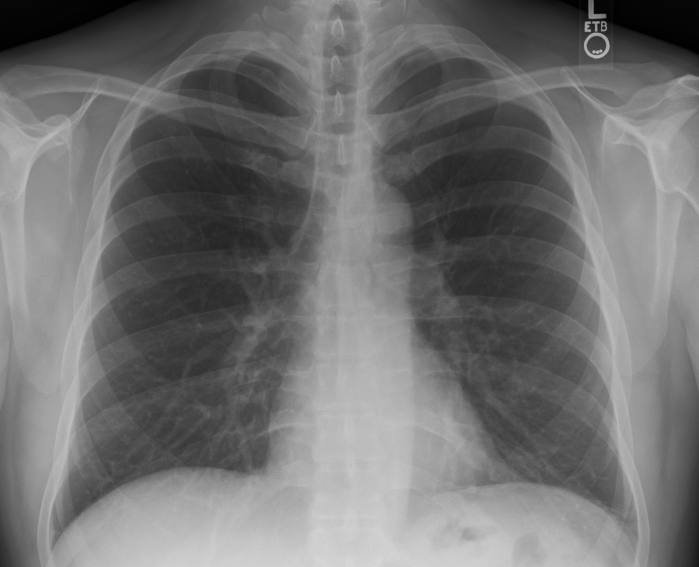

While eating breakfast this morning, our patient had a sudden onset of feeling like his heart was racing. He then developed shortness of breath, which has not improved. EMS was called by family when he got lightheaded standing up from the table. He is mildly confused and mentions mild chest discomfort.

A 72-year-old male presents with sudden onset palpitations and shortness of breath and is found to be in unstable atrial fibrillation with RVR. In the ED he is hypotensive with an altered level of consciousness and requires emergent cardioversion.